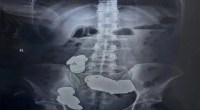

Elisany enfrenta o gigantismo, um crescimento excepcional, desencadeado por um tumor na glândula pituitária, responsável pelo controle do crescimento. Sua jornada já foi compartilhada em diversos programas nacionais, destacando a força e a resiliência diante desse desafio de saúde.

Desde os 11 anos, Elisany apresentava um crescimento notavelmente acelerado em comparação com o restante de sua família. Foi nesse período que o desequilíbrio hormonal foi identificado. Entretanto, somente aos 15 anos, ela se submeteu a uma cirurgia para remover o tumor e interromper o crescimento excepcional. A história de Elisany é um exemplo de superação e determinação diante das adversidades.